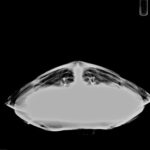

Patient Injuries

large hook penetrating through the eye curling back into mouth cavity, no other obvious injuries or abnormalities